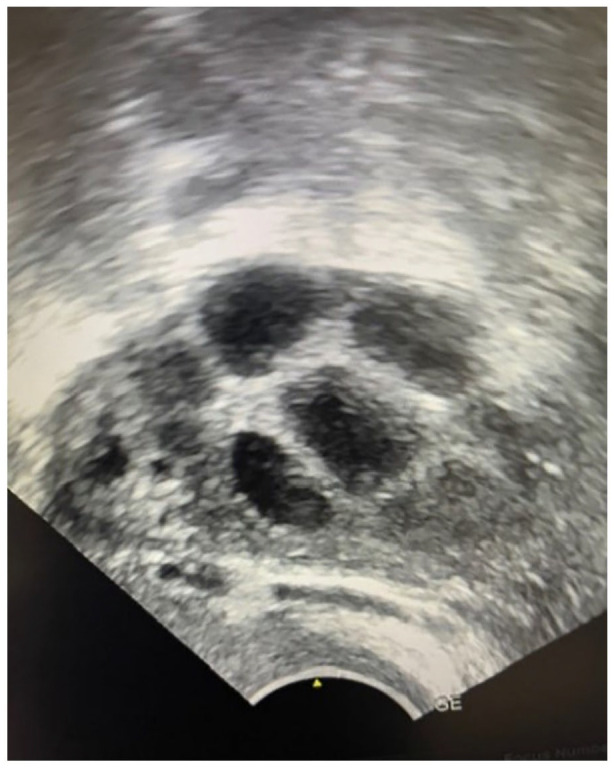

Abstract Image